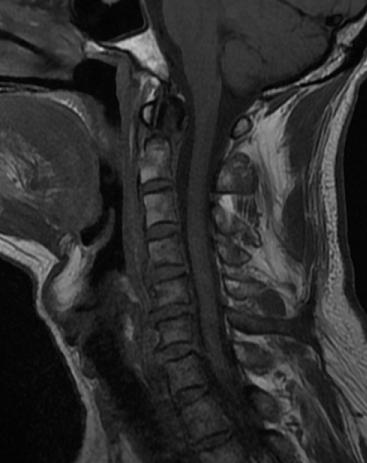

骨科主任医师唐海、单建林两位专家分析患者病情认为,王先生为枢椎齿状突的血运呈双侧雨刷状分布,保守治疗骨折不愈合的风险极大。行内固定手术无疑是最佳的选择,但是手术部位高位颈髓是生命中枢,手术难度极大,对术者的操作要求较高,如有不慎,会给患者带来灾难性后果。经过仔细地考虑,唐海与单建林为患者制定了详细的手术计划,决定实施枢椎齿状突骨折内固定手术。

术中,手术团队对王先生颈部重要的组织结构均进行了较好的保护,而且一次性成功的置入空心钉固定骨折断端。手术持续了近5个小时,术后王先生症状明显缓解,无神经损伤。术后复查X线显示齿状突复位,螺钉位置良好。目前王先生已顺利出院,并对北京友谊医院骨科中心的服务进行了高度的评价。